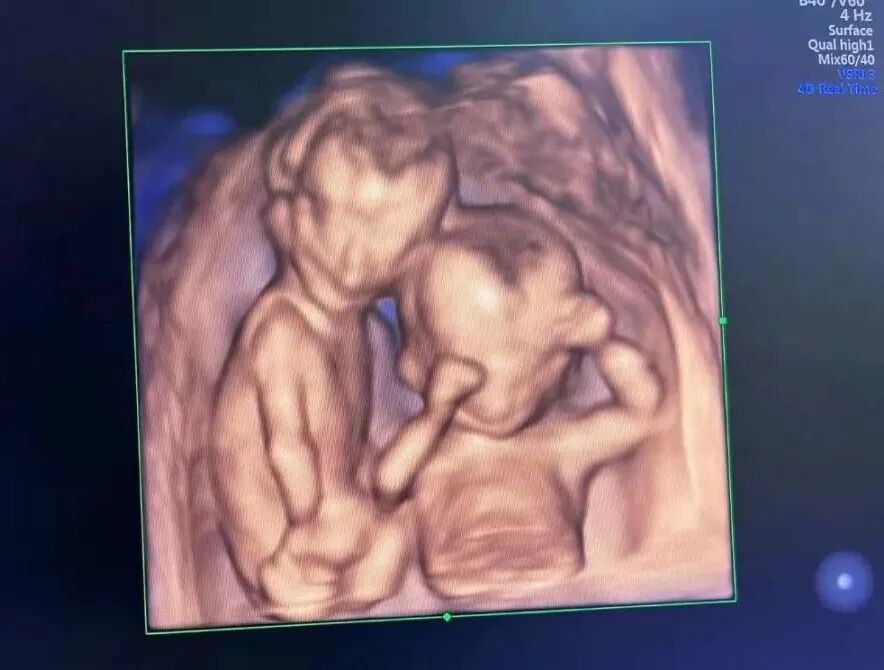

通过对宝宝双顶径、头围、腹围及股骨长等测量来评估宝宝的生长发育情况;

对颅脑、颜面部、胸腹部、心脏、脊柱及肢体等结构进行全面的筛查,可筛查出大部分严重结构畸形,如严重的脑膨出、严重的脊柱裂、严重的胸腹壁裂、致死性软骨发育发育不良、严重的肢体缺失等等;

评估胎盘、宫颈、宝宝活动度、羊水量等,测量脐动脉血流以间接判断宝宝营养供应情况,评估是否具有严重缺氧及宫内窘迫等;

如果您的宝宝足够配合的话,还可以拍一张漂亮可爱的四维照片。